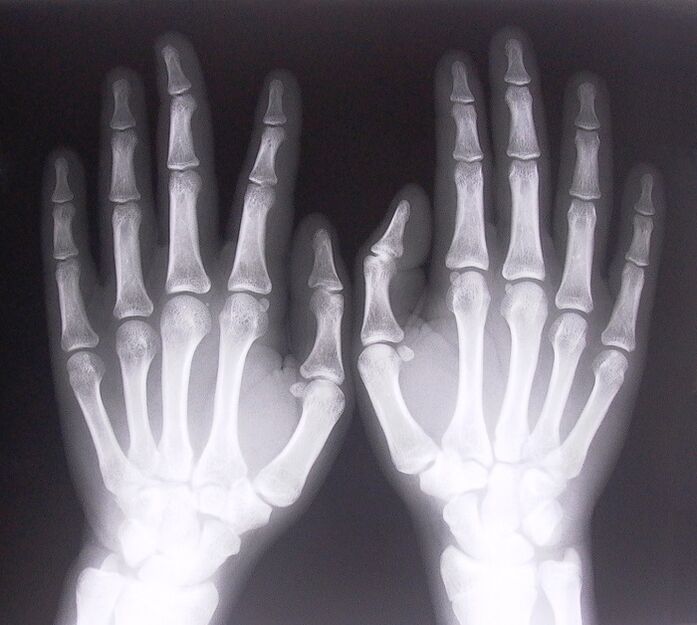

- Stenotizing ligamentitis.To identify the cause of the disease, an X-ray should be taken.The symptoms are typical: painful hand movement, clenched palm looping.Also, you will usually hear clicks during the extension.

- Take x-rays.